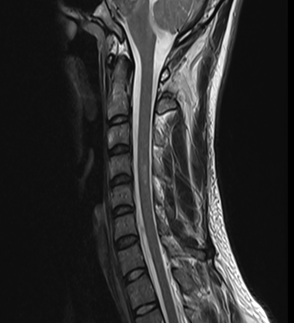

4.Lesiones de la médula espinal con lesiones similares que mejoran el T2 y el

gadolinio. (6)

2. RNM

d. Lesiones de la médula espinal con T2 y lesiones realzadas con gadolinio similares a las anteriores.